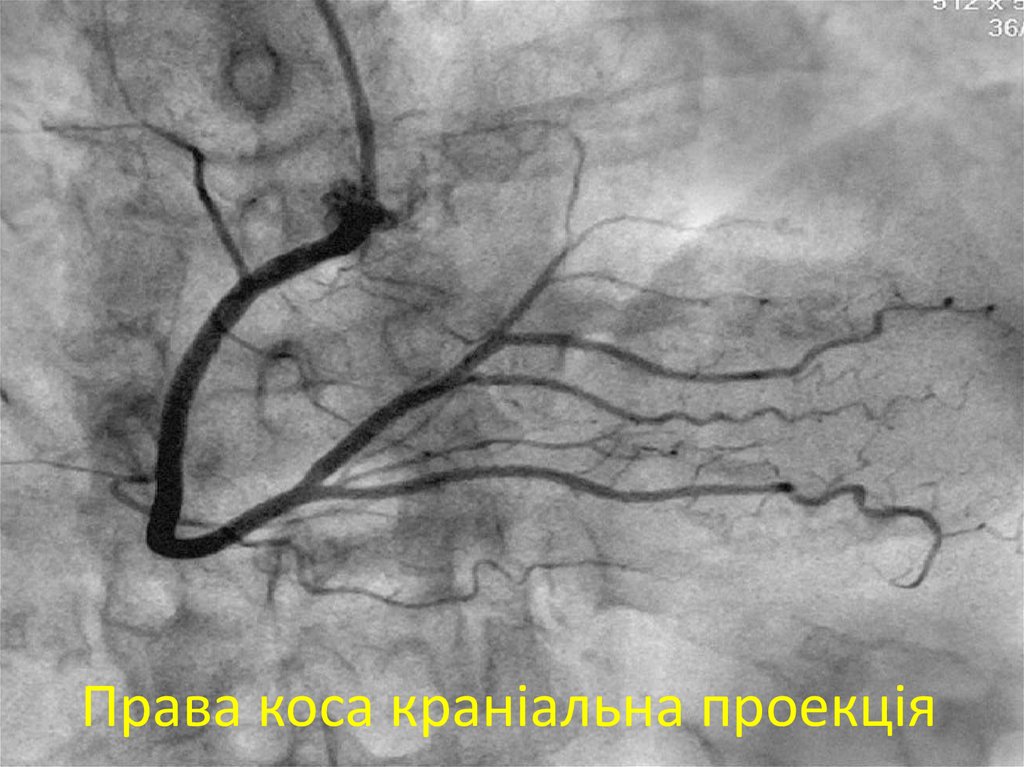

40. Права коса краніальна проекція

41. Права коса краніальна проекція

42. Права коса краніальна проекція